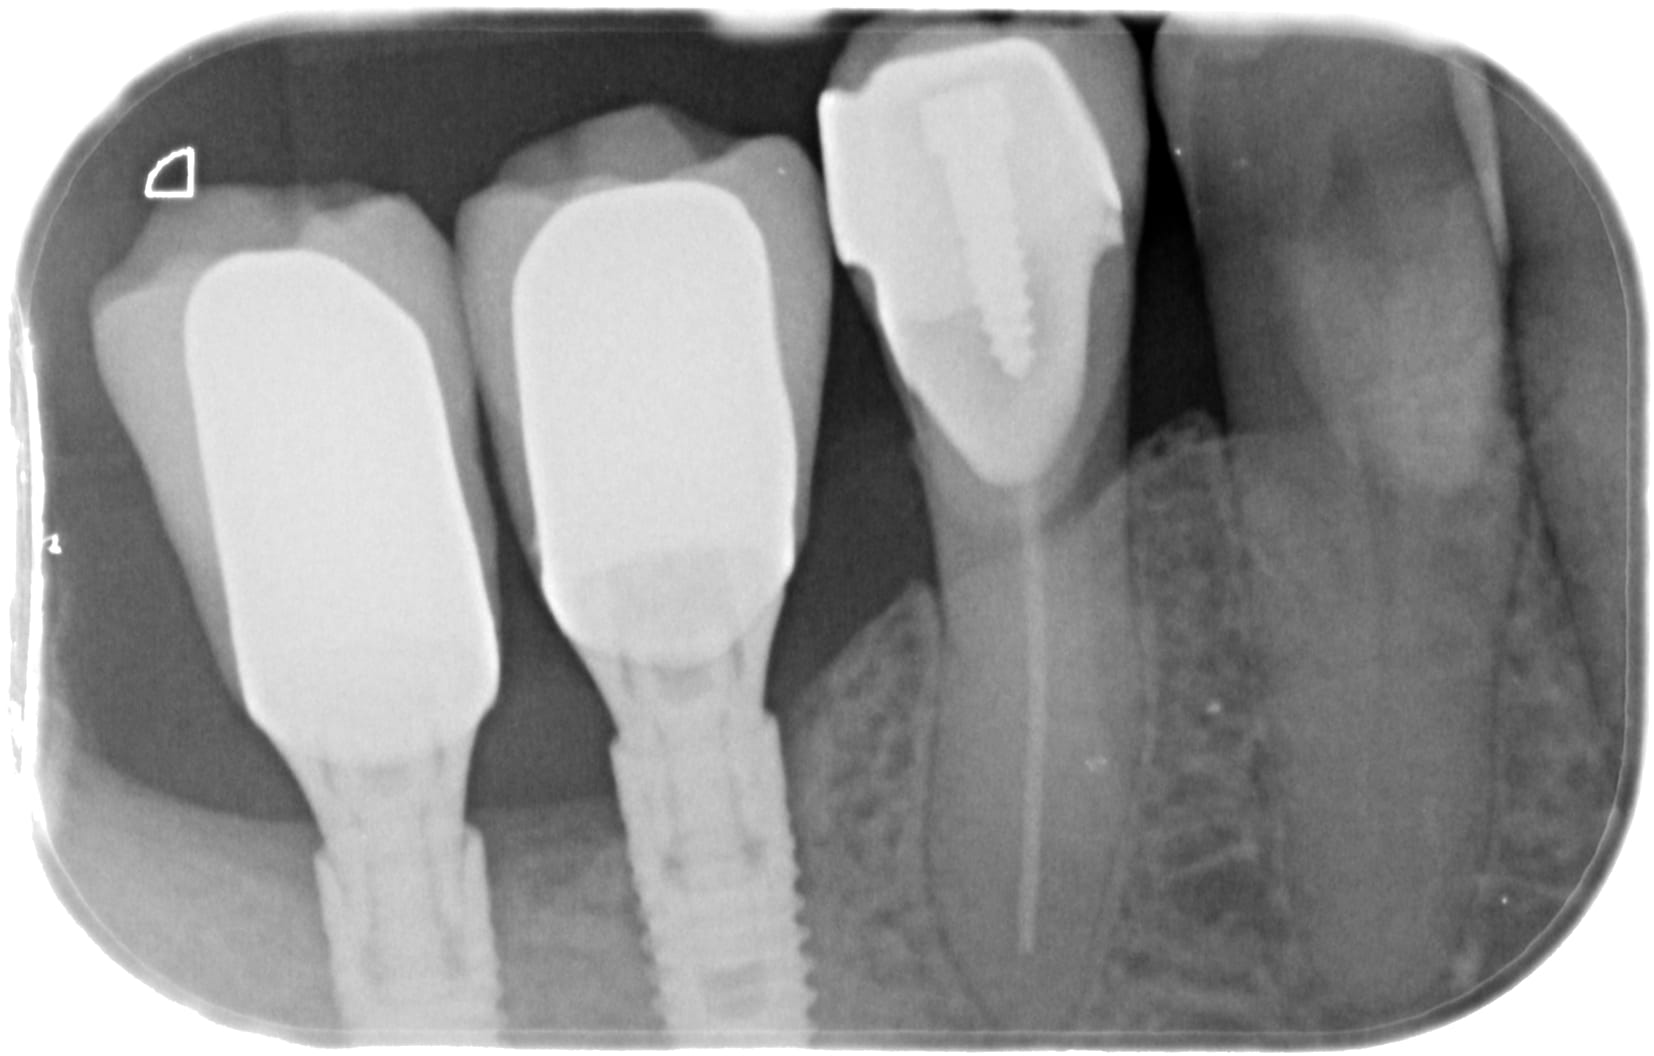

Pour la conjointe j ose pas tester... et j ai aucun pbm avec mes silicones donc j ose pas trop... et je fais beaucoup trop d ic ;))) et trop de sectorielles.

Mais serieusement, a mon avis une alginate bien traitée et preparation hurrimix, tu as du resultat en conjointe... mais attention aux déchirements.